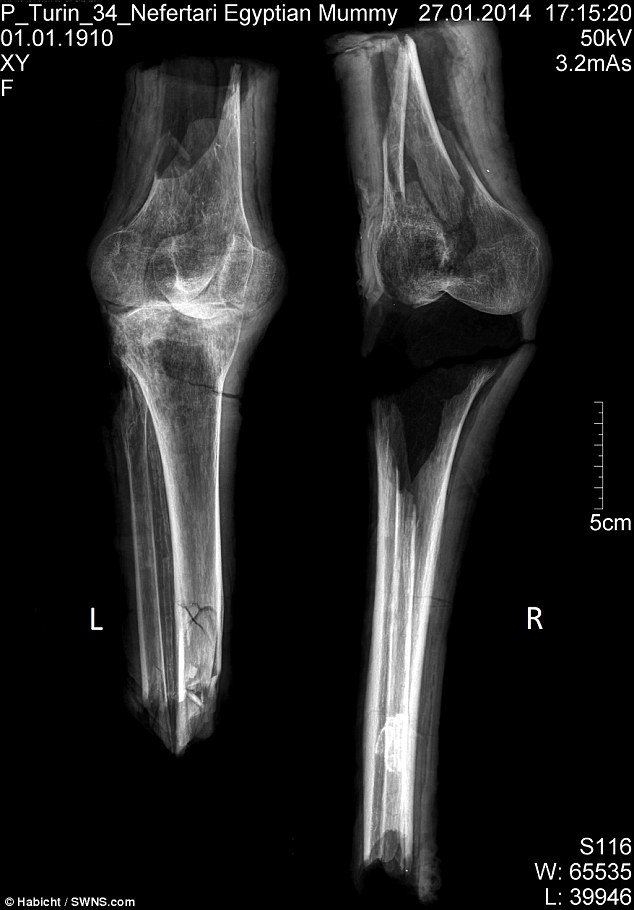

Mas uma nova análise realizada por uma equipe internacional, incluindo pesquisadores da Universidade de York, usou técnicas científicas modernas para confirmar a identidade das pernas. Os investigadores concluíram que as pernas pertencem a uma mulher de meia-idade, que media cerca de 1,65 m de altura que pode ter tido artrite.

Segundo especialistas, a pessoa devia ter entre 40 e 60 anos quando morreu – mesma faixa etária de Nefertari. De acordo com um artigo publicado pela revista PLoS ONE, “’o cenário mais provável é que os joelhos mumificados realmente pertençam à rainha Nefertari”, afirmam os cientistas.

Usando análises químicas, datação por radiocarbono e análise de DNA, eles descobriram que o bálsamo usado no processo de mumificação condizia com o utilizado durante o reinado de Ramsés. As evidências sugerem que as pernas pertencem à Nefertari e não a suas filhas – que foram enterradas no mesmo túmulo.

“Nós só podemos supor que ladrões de tumbas tenham separado o corpo dos cadáveres enquanto procuraram amuletos de ouro e prata dentro dos invólucros. Pensamos isso porque só os joelhos mumificados sobreviveram. O resto do seu corpo permanece um mistério”, disse Fletcher.